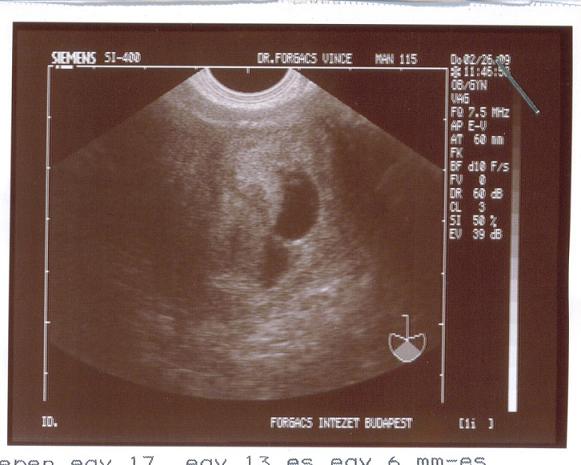

Szóval a mai eredményünk:

"TVS során a méh üregében egy 17, egy 13 és egy 6 mm-es petezsák látható. A legnagyobb másodlagos szikhólyag és egy élő embrio látható. A középső petezsákban embrionális elem látható, de életjelenség még még nem igazolható. A legkisebb petezsákban embrionális elem nincs.

A méh környezetében kóros képlet nem látható.

Ikerterhesség"

Képet is kaptam, de sajna ismét bekerepált az asztali gépünk, amin van a kicsinyítő programunk.

Ja, a doki szerint tuti, hogy nem lesz három babánk. Ketteskét pedig két hét múlva megint megkuksizzák.